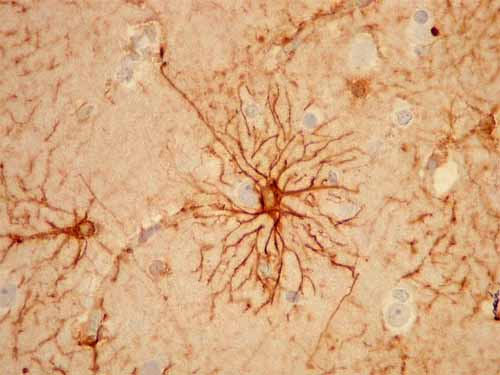

Astrócitos – Existem dois tipos destas células:

.     Protoplasmáticos: com várias ramificações curtas, essencialmente na matéria cinzenta;

Fig-4 – astrócito protoplasmático